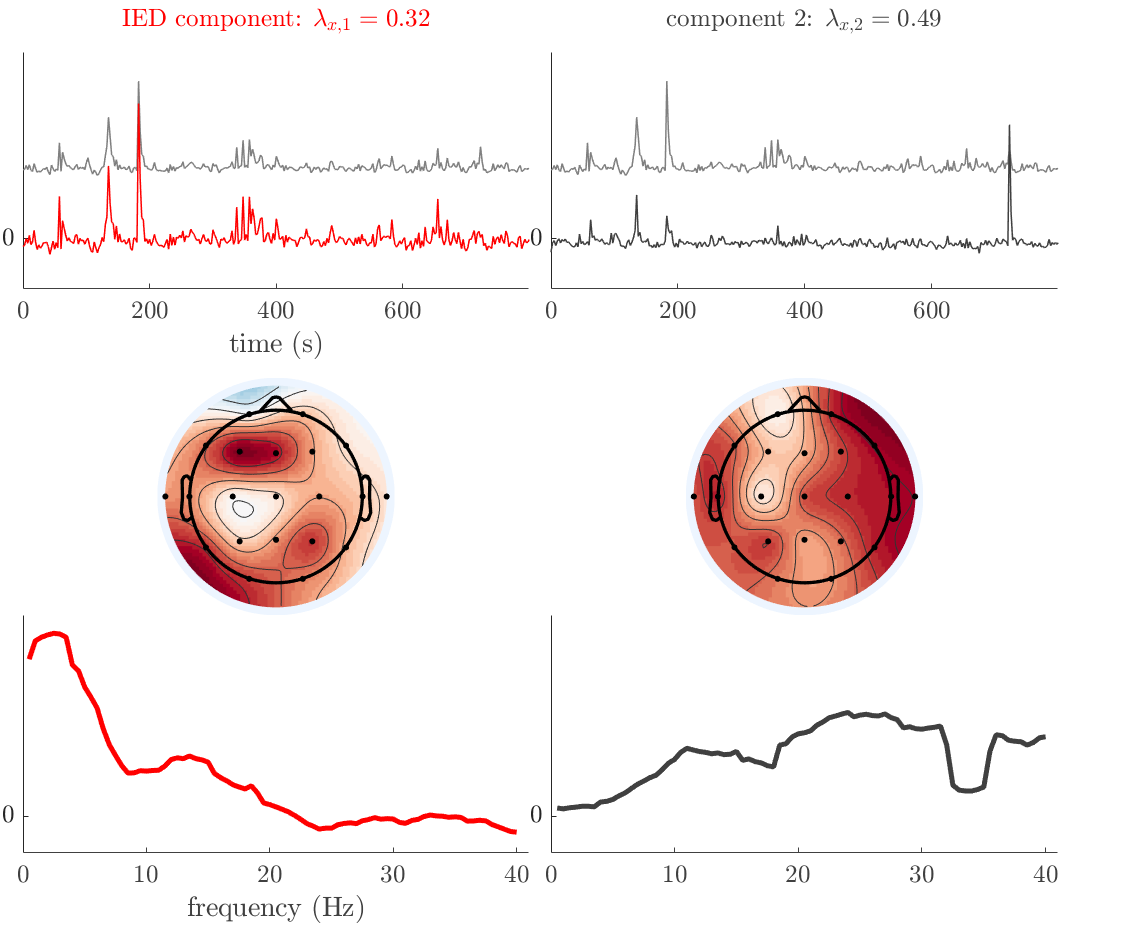

Patient 2

We analyze the solution with sources, and show the results in Figure 3 and 4. As for patient 1, we found a source which is strongly correlated to the MWF envelope, and which had a mostly low-frequency behavior characteristic for spikes. The topography is mostly uninformative, and does not clearly correspond to the patient’s clinical data. The third source is mostly present at both sides of the head, is very sparsely active in time, and has a high-frequency content: this is most likely an artifact due to the neck muscles. Again, there is one of the highest-entropy HRFs which belongs to a ROI in the IOZ. Now, the waveform is clearly resolved from the other HRFs, through the strong initial dip (before 0 seconds). Such a dip is sometimes observed in HRFs, but its underlying physiological mechanism is not yet fully understood. It is possible that this dip reflects altered vascular autoregulation near the IOZ (cfr. the explanation in the Section 1 of the main text), or a rapid depletion in oxygen due to IED generation (before the IED becomes visible on the EEG). Figure 4 furthermore shows that the IED-related component is significantly active in parts of the IOZ, and deactive in others. As mentioned earlier, this deactivation may or may not be due to errors in sign correction. Interestingly, the ROI with the high alteration in neurovascular coupling is distinct from both the activated and deactivated ROIs.